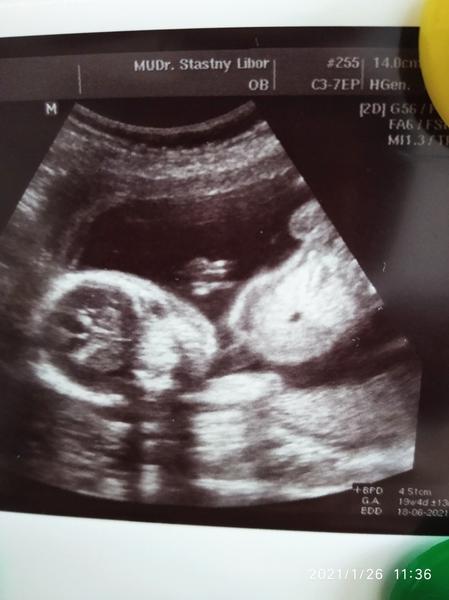

@lili1688 Pokud jste pozorovala utz, tak jste si jiste vsimla, ze se miminko ruzne hybe a doktor zameruje ruzne casti tela nebo je dokonce prosviti.

To, co mate zakrouzkovane muze byt cokoli co se vyskytuje okolo hrudniku nebo bricha. Miminko se zrovna hybalo a doktor udelal screen ve chvili, kdy se tam proste zobrazilo “tohle”.

Pohlavi to urcite neni a dal je asi jedno co to je, ne? 🤷🏼♀️